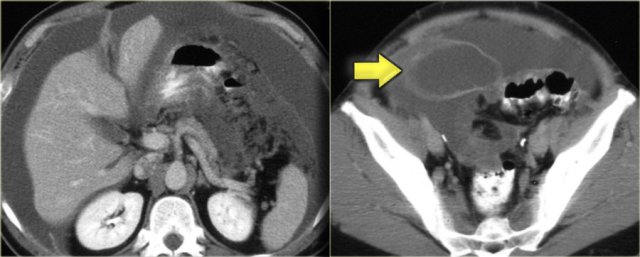

Pseudomyxoma peritonei (2)

On the left another case of pseudomyxoma peritonei.

There is hardly any scalloping of the liver.

Notice the thickened falciform ligament.

There is a mucocele of the appendix (arrow).

This finding is only rarely seen.

There is compression of the mesentery resulting in a thickened cake-like hyperdense mesentery (arrow).

There are also some calcifications.

Pseudomyxoma peritonei is often confused with mucinous carcinomatosis.

Unlike carcinomatosis it does not have true omental tumor deposits presenting as omental cake or peritoneal tumor deposits.